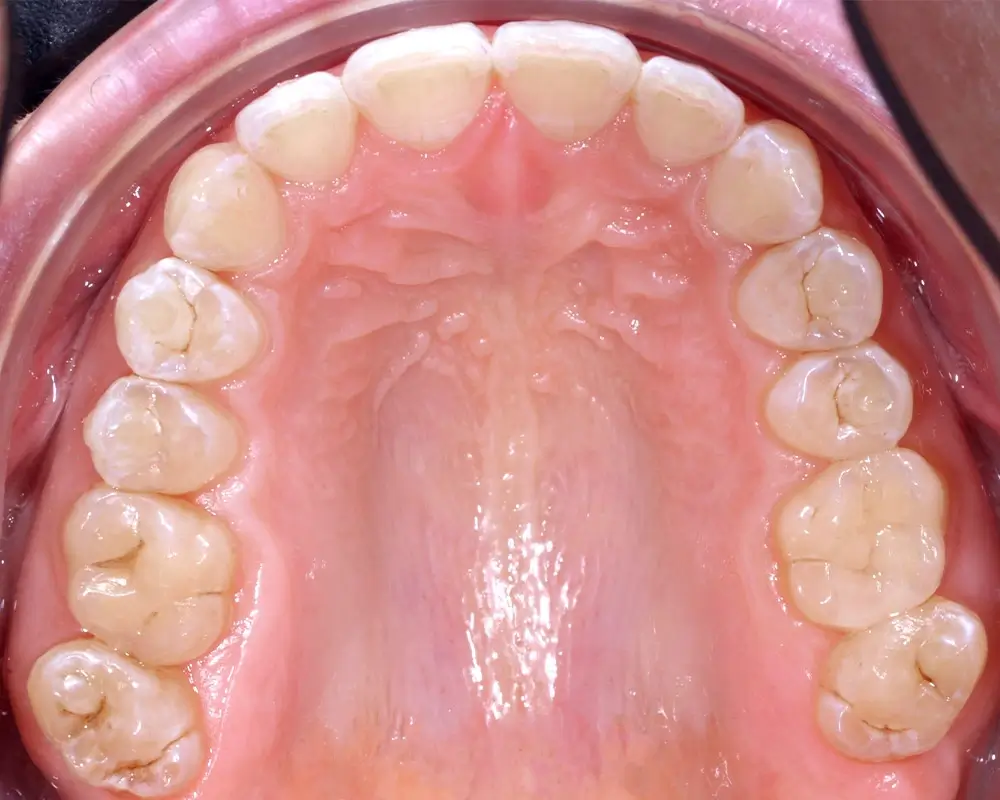

Кейс 1

Бажанова Ольга Валерьевна

Количество кап ВЧ 25

Количество кап НЧ 25

ДО

ПОСЛЕ